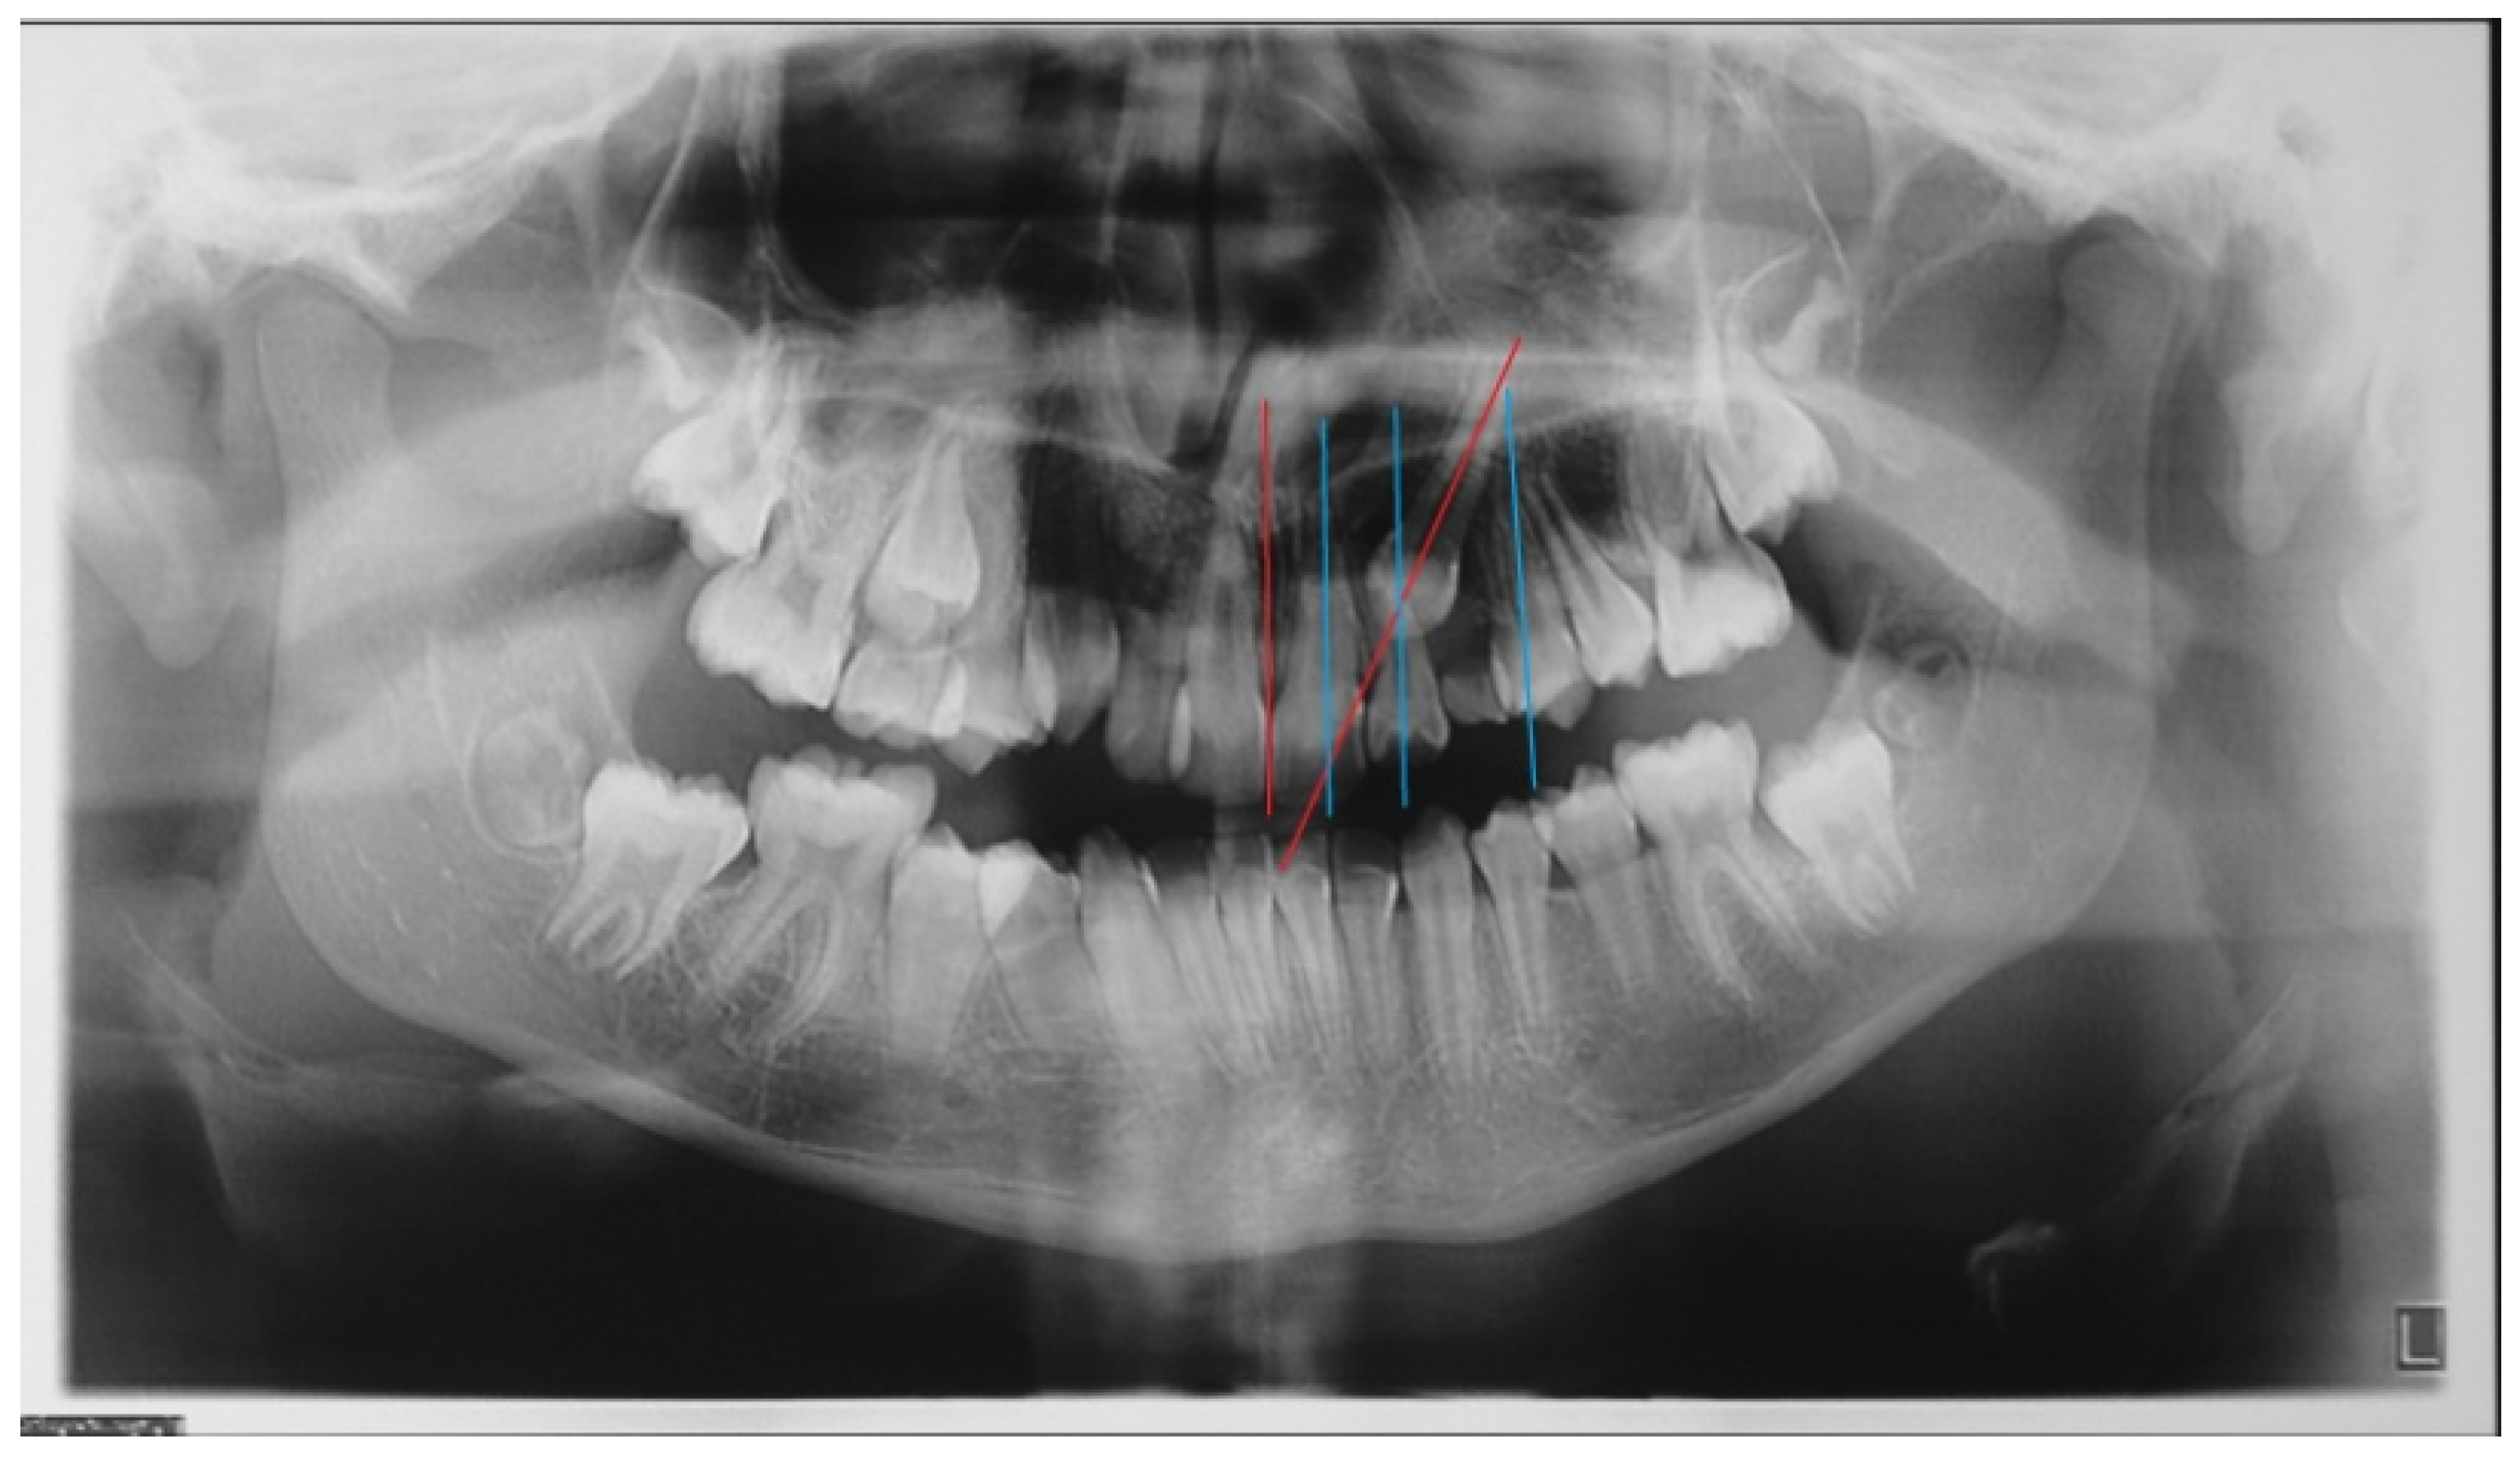

- In the first step, a panoramic radiograph and a teleradiography of the skull in latero-lateral projection is required. The observation of the panoramic radiography should show the position of the impacted canine, evaluating the relationships of the canine crown with the roots of the adjacent teeth, the alpha angle, and the distance of the impacted tooth from the occlusal plane. The cephalometric study of the teleradiography should provide information about the eventually present malocclusion and treatment needed;

- Mesioinclinated Canine in Close Relation to The Root of The Lateral Incisor: In cases of vestibular canine impaction, a tight relation between the canine crown and the lateral incisor root is often visible. Every so often, moreover, the lateral incisor presents with a horizontal displacement due to the pressure of the erupting mispositioned canine. This condition frequently correlates with an increased risk of root resorption for the lateral and sometimes also for the central incisor. An orthodontic force applied on the canine crown and directed with a distal and occlusal vector could increase the probability of pressure, due to the fact of this latter component, and could therefore increase the risk of root resorption. Conventional treatment should provide a traction arm in a high position and with a horizontal force direction, thus increasing the patient’s discomfort and the likelihood of eruption in free mucosa. Complex and multidisciplinary cases are particularly prone to this difficult operating condition with wide areas of contact between roots and crowns of impacted teeth [24,25]. In any case, a previous evaluation of the disimpaction prognosis is mandatory (angulation, better if the impacted tooth is mesio-angled, α angle, and sector S of localization of the crown according to the classification of Ericson and Kuroll modified by Baccetti [22]).